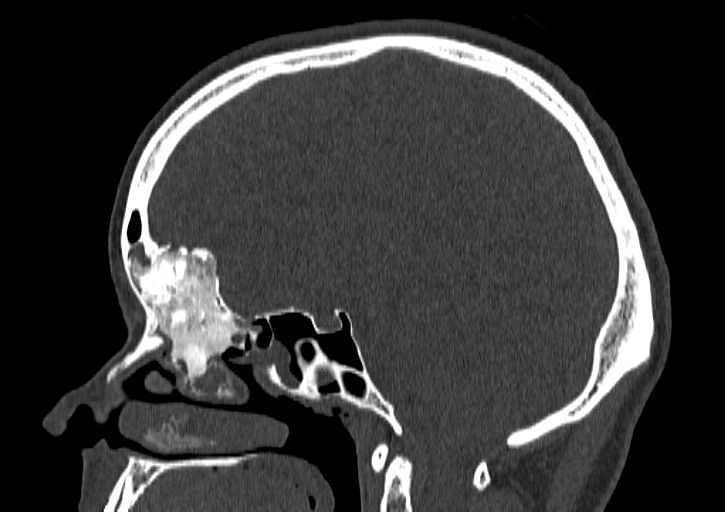

Prof. Paweł Słoniewski from the Clinic of Neurosurgery and Andrzej Skorek M.D. Ph.D. from the Clinic of Otolaryngology have their first successes related to the treatment of pathological diseases of nasal sinus and brain. Interdisciplinarity of the treatment is a response to the increasing number of patients suffering from the mentioned above diseases. The specialists worked on improving security of a patient during a surgery. So far they operated 6 patients (2 with malignant and 4 with non-malignant tumors) whose base of a skull frontal bone, meninges and tumors were resected and then a durable and impermeable barrier separating the inside of the skull and the nasal cavity was recreated. The surgeries were carried out at the Invasive Medicine Centre. No complications were recorded.